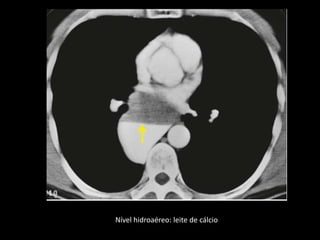

Nível hidroaéreo: leite de cálcio

Cisto Broncogênico(CB) É de longe a forma mais comum de cisto de duplicação do intestino anterior resultante de uma má separação ventral com a árvore traqueobrônquica; Cerca de 80% dos casos ocorrem nas regiões paratraqueal ou subcarinal; Os CB são malformações císticas congênitas dos pulmões raras e apenas de 10-30% apresentam localização intrapulmonar;

• 22.

Cisto Broncogênico(CB) Todosos CB apresentam uma camada de epitélio respiratório e podem conter cartilagem; Caracteristicamente, os CB não se comunicam com a árvore traqueobrônquica até que se tornem infectados; Os CB n parênquima pulmonar podem estar associados à hiperinsuflação e ao aprisionamento aéreo, como resultado de um mecanismo de válvula ou atelectasia pós-obstrutiva.